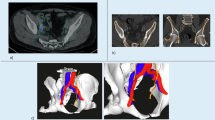

Pelvic lymph node dissection (PLND) is integral to prostate cancer staging, but its therapeutic value remains debated. PSMA PET/CT has shown high accuracy in detecting lymph node metastasis (LNM). This study evaluates the feasibility of performing PLND based on PSMA PET/CT findings during robotic-assisted radical prostatectomy (RARP).

In this prospective, randomized study, biopsy-confirmed prostate cancer (PCa) patients with intermediate or high risk were enrolled. Patients with distant metastasis or prior endocrine therapy were excluded. All underwent 18F-PSMA PET/CT imaging, and those with LNM were assigned to Group A. Patients without LNM were randomized in a 1:1 ratio into Groups B and C. All patients underwent RARP and Groups A and B with PLND while Group C without. The primary outcomes were PSMA PET/CT accuracy in detecting LNM and oncological results. This trial is registered with the Chinese Clinical Trial Registry (ChiCTR2200063256).